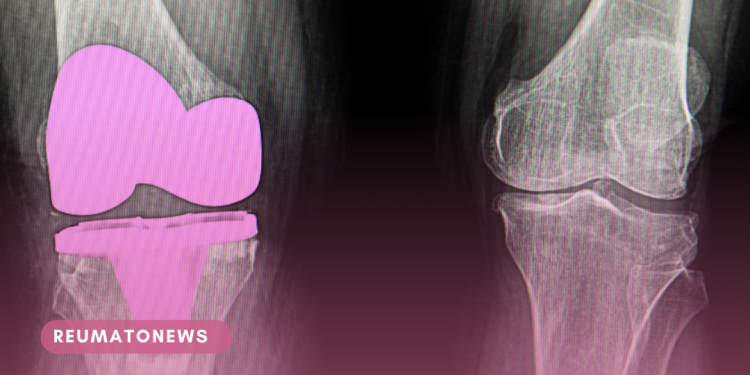

Considerada uma das doenças mais incapacitantes e responsável pelo comprometimento da qualidade de vida das pessoas que sofrem com a rigidez nas articulações, além de dores indescritíveis, a artrose do joelho degenera as cartilagens que envolvem as extremidades ósseas.

Em alguns casos, somente a substituição da articulação por um dispositivo médico implantável é capaz de eliminar o problema.